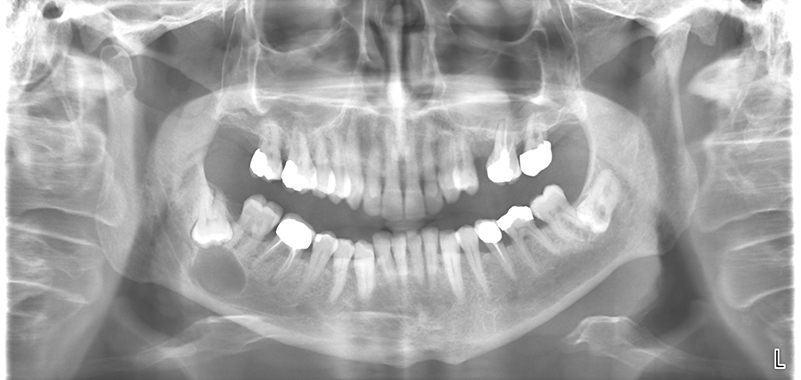

La radiografia del mese

Multidisciplinarietà diagnostica e terapeutica nelle patologie orali e faringee